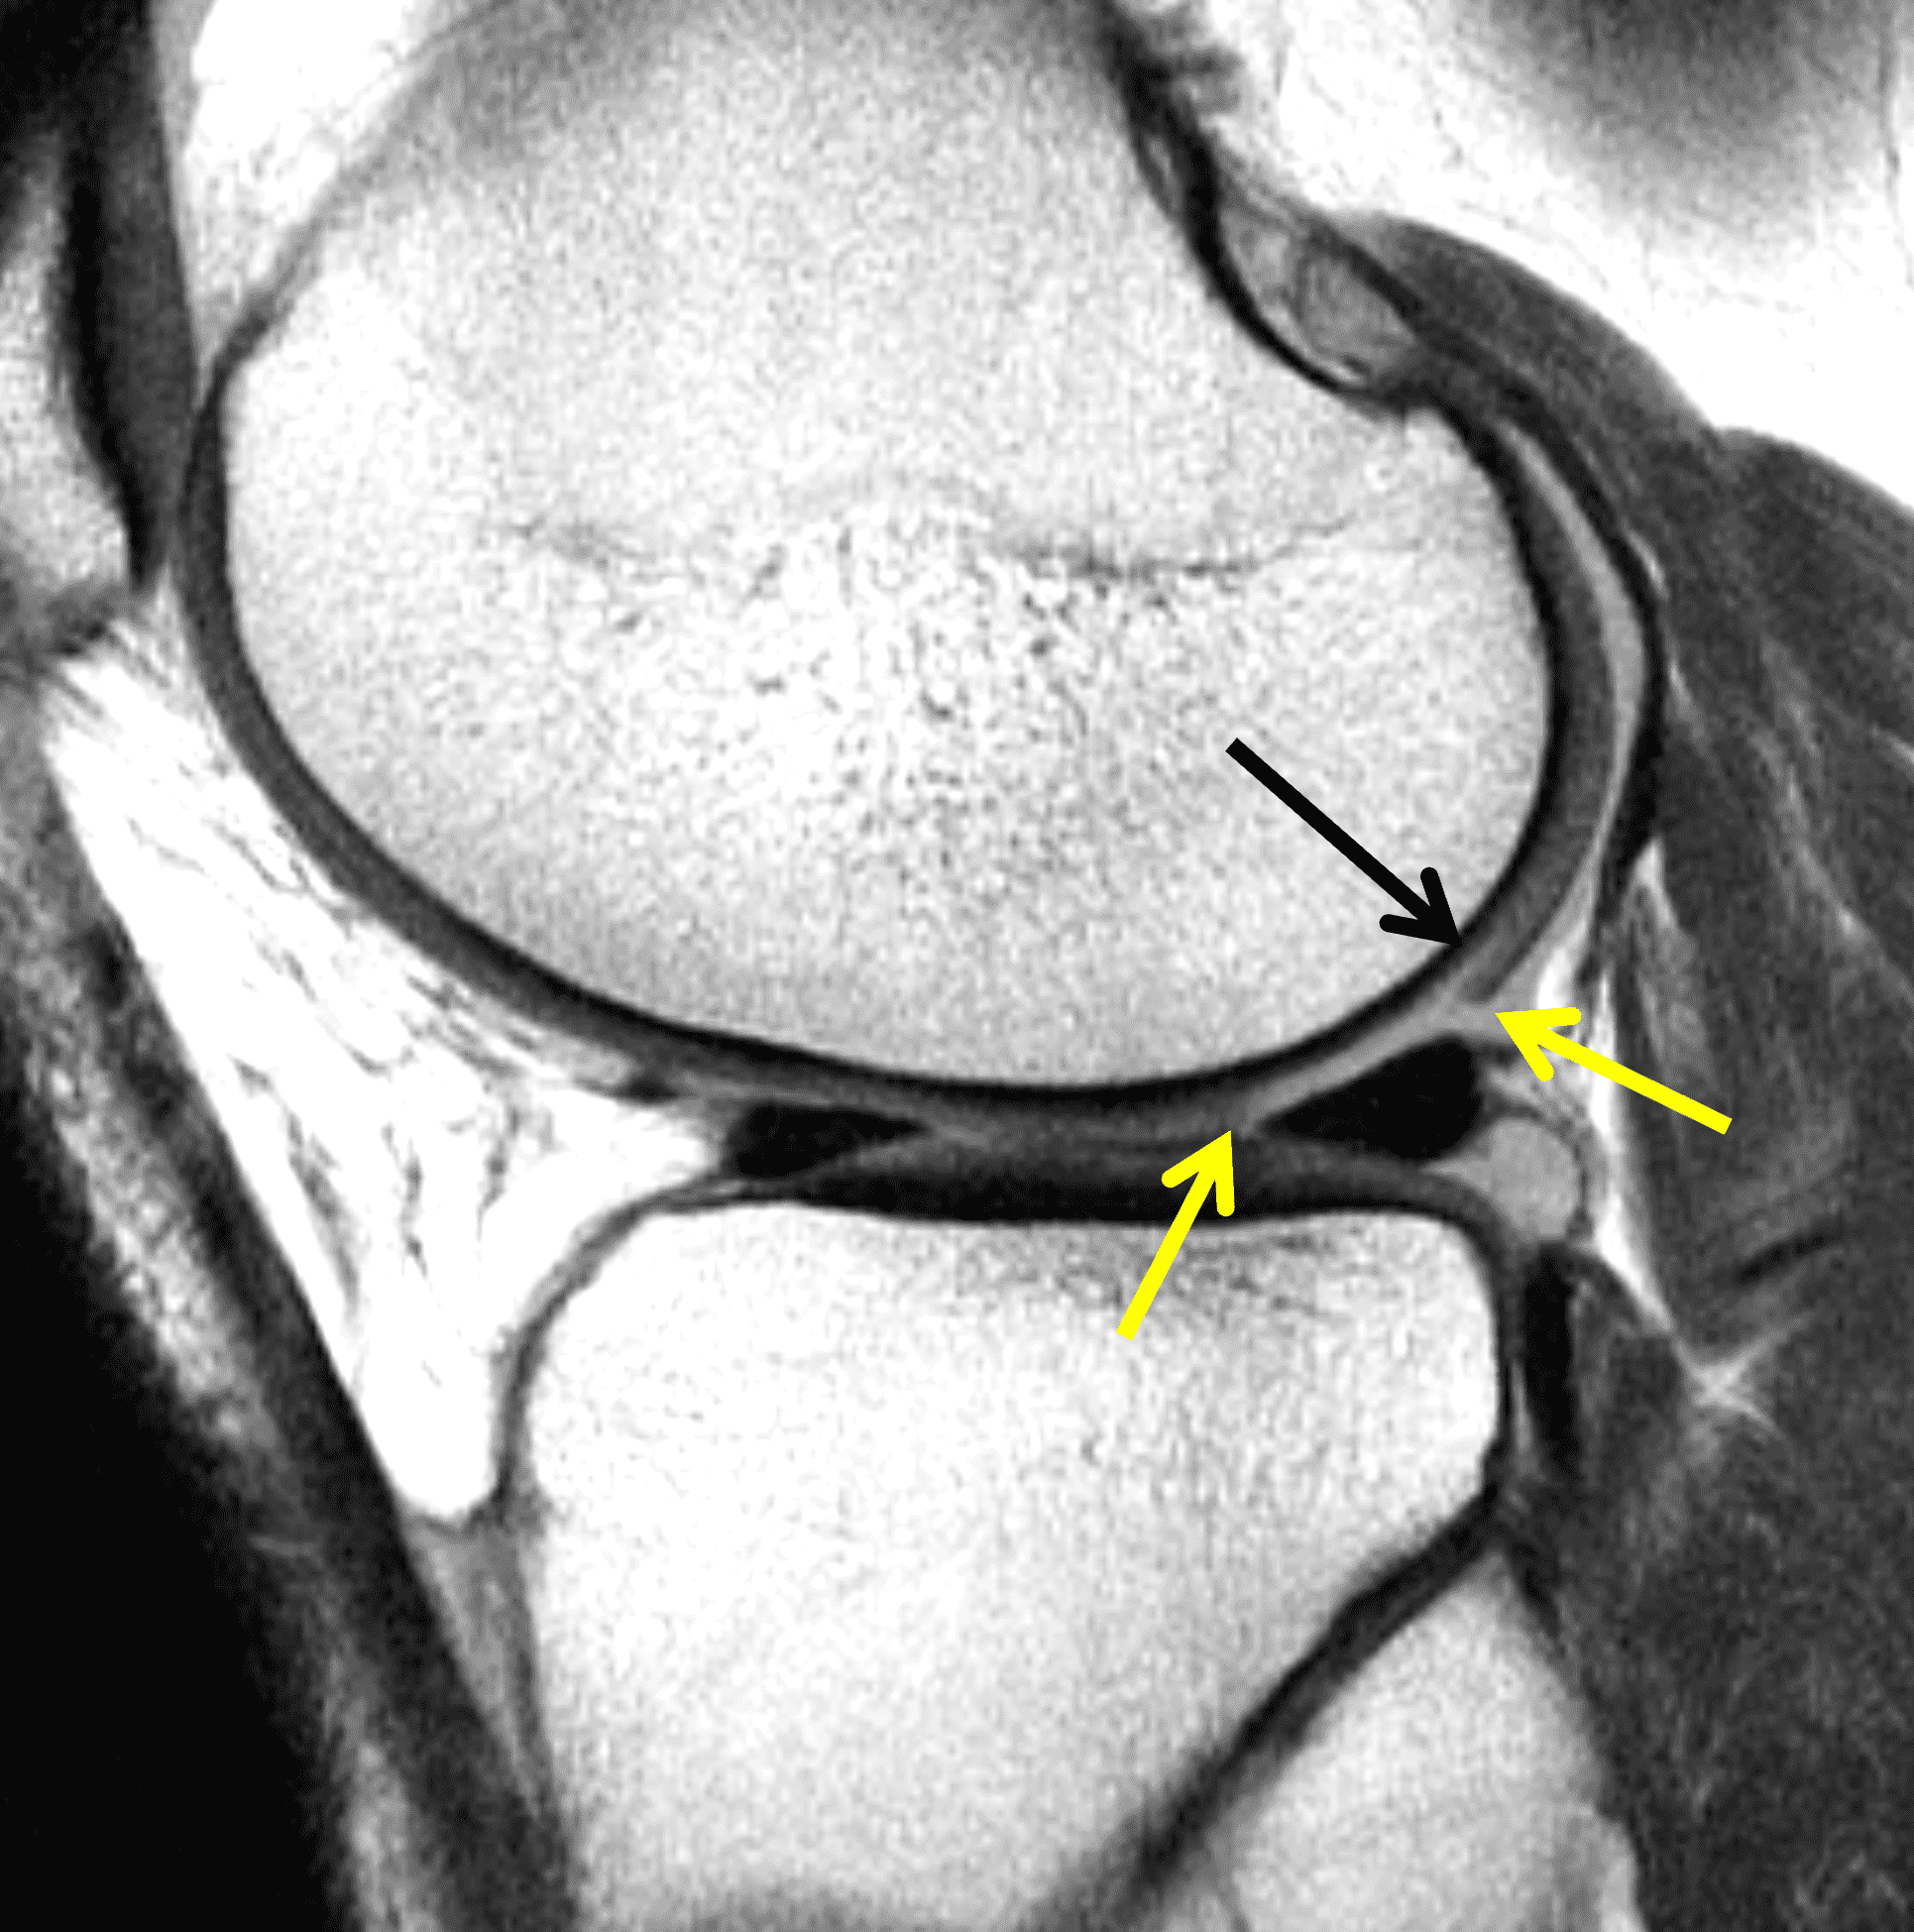

Because the thickness of the transplanted cartilage may differ from that at the recipient site, a step-off in the subchondral bone plate can be visible at the junction between the lesion and graft as a normal finding (Figure 14). The articular surface of the graft, however, should be congruent and flush with the surrounding cartilage on MRI. Marrow edema surrounding the graft is common in the first 3-9 months. The signal intensity within the transplanted cartilage can be variable, and like marrow changes, may take up to 3 years to normalize.29 Successful grafts will show incorporation of the transplanted bone with the surrounding bone (Figure 15). Cyst developmental at the base of graft may be a clue to poor incorporation (Figure 16) but can also be an incidental finding. Other than bone integration and surface congruence, most MRI findings have a weak correlation with outcomes. Osteonecrosis of the graft is a rare complication characterized by low signal intensity in the graft on T1-weighted images and lack of intravenous enhancement; however, graft osteonecrosis does not necessarily correlate with outcomes.24 Over time, osteochondral autografts may fail through development of degenerative arthritis with fissuring of the articular surface and cartilage loss (Figure 17).

The postoperative imaging appearance of osteochondral allografts is similar to autografts (Figure 2).33 The subchondral bone plate of the donor and recipient sites do not have to match, but the articular surface should be congruent. Grafts that fail to incorporate by one year have a poor prognosis. Persistent marrow edema (beyond 12 months), a thick graft interface containing cysts or fluid, and subsidence of the graft are associated with poor osseous healing and worse outcomes. Extensive host marrow edema and severe synovitis may be a clue to immunologic rejection of the graft (Figure 18).21, 34